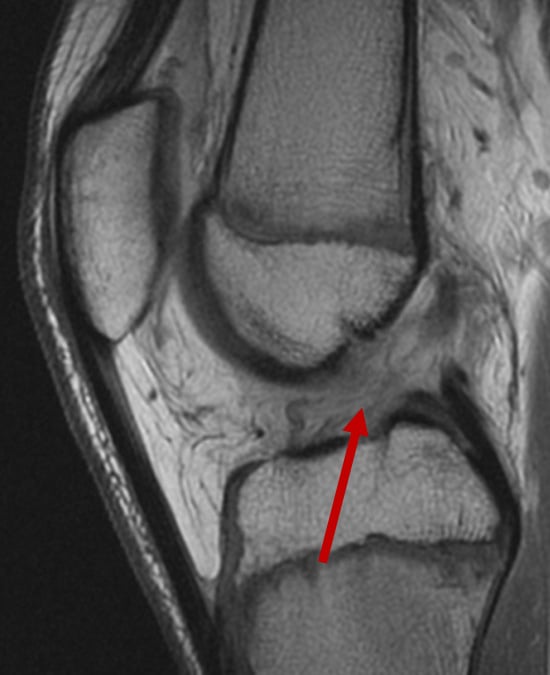

MRI showing a completely torn anterior cruciate ligament.